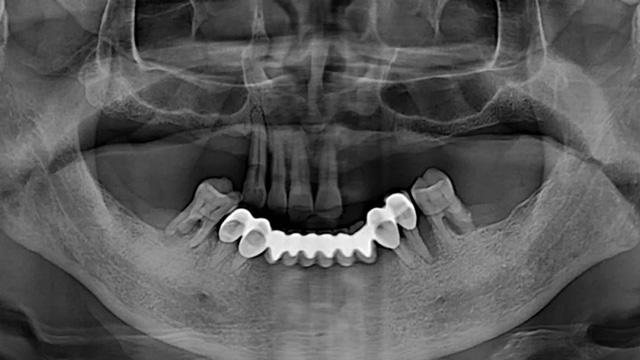

王先生的口腔全景片(2021年9月/新橋口腔成都玉雙院區(qū))

60歲出頭時(shí),王先生嘴里還剩下10顆牙,尷尬的是,上下有牙的地方剛好完美錯(cuò)開。上面雖有4顆前牙鎮(zhèn)守門面,無奈下面的6顆牙卻分散在左右兩側(cè),完全碰不上。為了能吃東西,他去診所給下牙安了一個(gè)烤瓷聯(lián)冠,用……

60歲出頭時(shí),王先生嘴里還剩下10顆牙,尷尬的是,上下有牙的地方剛好完美錯(cuò)開。上面雖有4顆前牙鎮(zhèn)守門面,無奈下面的6顆牙卻分散在左右兩側(cè),完全碰不上。為了能吃東西,他去診所給下牙安了一個(gè)烤瓷聯(lián)冠,用左右各兩顆牙當(dāng)做橋墩做了一個(gè)超長的橋架。

這半口形態(tài)失真、歪歪扭扭的牙看起來似乎還將就,但一張嘴就露餡了,特別是和親友一起吃飯時(shí),如推磨般的咀嚼功能讓他非常惱火。幾年后,王先生聽說種植牙比較好用,去了新橋口腔等好幾家醫(yī)療機(jī)構(gòu)咨詢,最終因?yàn)橘M(fèi)用問題和種種顧慮,沒有種植。